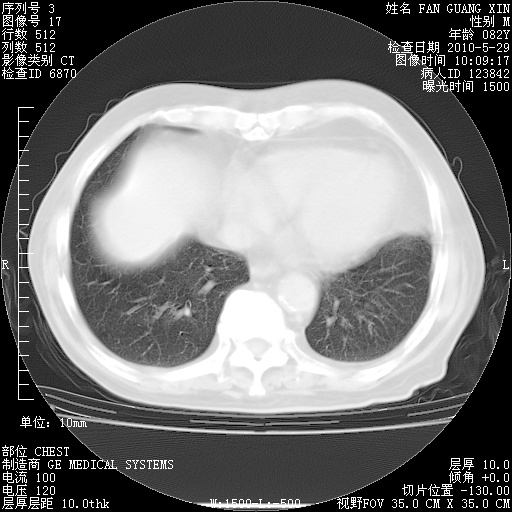

再治疗10天后的肺部CT 纵膈窗

阅读此次胸部CT,肺间质渗出性改变较入院时有吸收。目前从体温、白细胞、中性分叶明显增高,肯定存在细菌感染(发生医院感染哦,若无消化道及泌尿系统等感染的依据,肺部感染可能大)。若你院头孢哌酮舒巴坦钠耐药率较高,同意你的方案,若48小时体温仍高,可考虑使用碳青霉稀类抗菌药物,同时可予超声雾化、注意滴数时加大液体量。白蛋白33.30g/L较低哦,需加强营养等支持治疗。